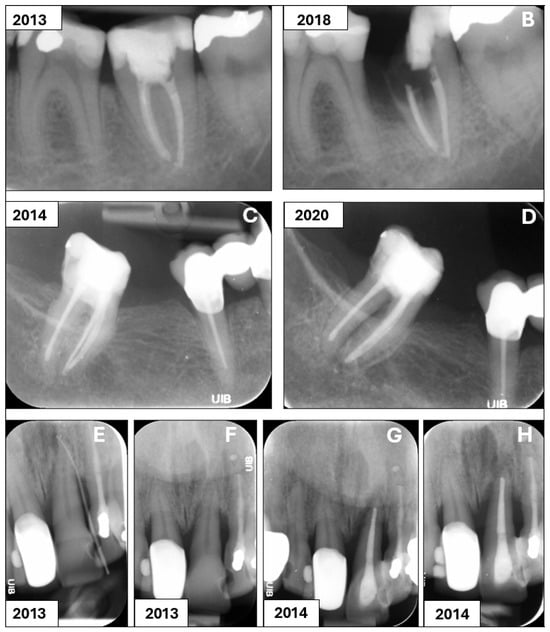

All 32 extracted teeth were removed for non-endodontic reasons, including unrestorable carious lesion (38%), progression of periodontal disease (28%) or tooth fracture (34%). Representative radiographs are presented in Figure 2.

Figure 2. Representative radiographs of teeth extracted due to carious lesion (A,B), tooth fracture (C,D) and periodontal disease (EH). Tooth 37 was root filled in 2013 (A). An expanding carious lesion resulted in an unrestorable tooth that eventually was extracted in 2018 (B). Tooth 47 was root filled in 2014 (C). In 2020, the patient experienced severe pain of sudden onset for 2 days. Clinical examination showed endodontic pocket to apex and tooth was extracted due to fracture (D). Tooth 21 was diagnosed with pulp necrosis and periapical abscess with sinus tract (E,F). Tooth was root filled in 2013, and a six-month (G) and one-year recall (H) showed progression of periodontal disease. Tooth 21 was eventually extracted.